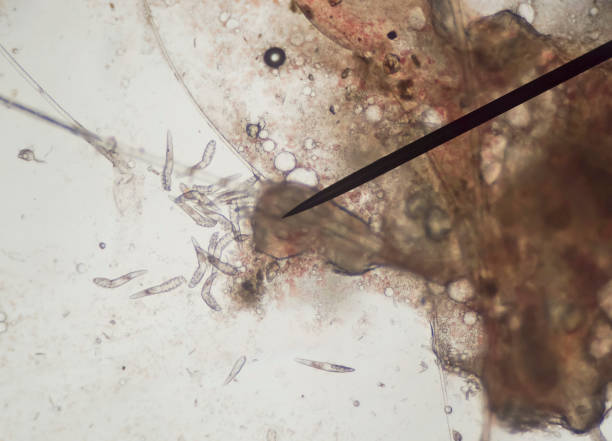

Файл:Demodex mite 1.JPG - Википедия